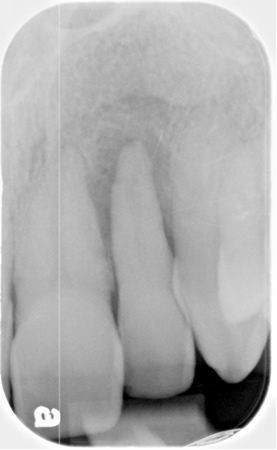

At the initial visit in June 2010, special attention was paid to the six teeth that were in danger of extraction (numbers 2, 3, 7, 10, 14 and 15). Upon reviewing the full-mouth x-ray, Dr. Wilson expressed particular concerned about tooth #10, which exhibited class III mobility and excessive bone loss. The only thing that appeared to hold this tooth in place was diseased gum tissue which a laser removes. If the patient insisted on attempting to save this tooth, not only was the concern that the tooth would exfoliate, but also that the patient might experience such severe post-operative pain that he would want the tooth extracted immediately. Compounding the problem was the fact that the patient lives over 200 miles from the office. By the time he returned home, the effects of the anesthetic would have worn off and the post-operative pain would have set in.

In March of 2011, at the nine-month mark, the patient returned for evaluation. A periodontal maintenance was completed and the most threatened teeth, # 10 and #14, were evaluated. Neither tooth exhibited mobility. Additionally, periapical radiographs were taken of both to evaluate the bone. The results were unexpectedly positive, and the patient was referred to an endodontist for root canal therapy on #14. Dr. Wilson performed root canal therapy for #10. All work was completed by July 28, 2011.